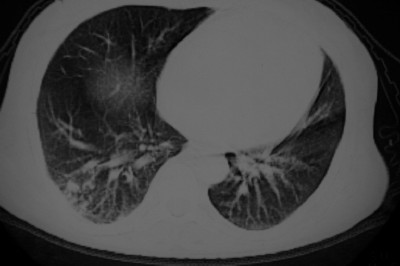

以下是引用天南地北在2007-4-10 1:49:00的发言:[br]考虑右下叶周围型肺癌伴肋骨转移。

以下是引用jone-baby在2007-4-10 8:45:00的发言:[br][br] [br] 患者[br]有发热史,x线片考虑肺脓肿.肺脓肿可以导致肋骨破坏吗?[br]脓肿可以排除吗? [br] [br] [br]

以下是引用林建春在2007-4-10 7:35:00的发言:[br]周围型肺癌侵犯肋骨

以下是引用liuyue在2007-4-10 7:56:00的发言:[br]周围型肺癌侵犯肋骨,左肺转移。

以下是引用zhangzhongshou在2007-4-10 10:24:00的发言:[br]右肺下叶背段厚壁空洞,伴胸膜改变、肋骨破坏,其内可见死骨、周围骨质硬化,左肺可见小结节影,[br]单纯影像学更支持结核。建议进一步检查。